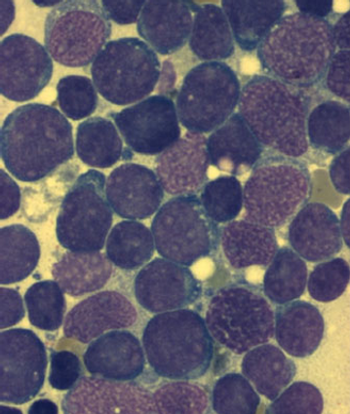

The oral BCL-2 inhibitor venetoclax elicited a high rate of response from patients with high-risk relapsed or refractory chronic lymphocytic leukemia with 17p deletion.